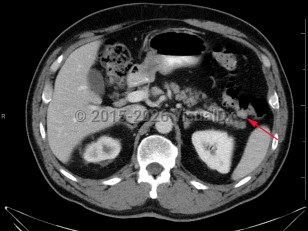

Colonic polyps

Histologically, polyps may be tubular, villous, or tubulovillous. Villous adenomas are 3 times more likely to become malignant than tubular polyps. The likelihood that a polyp contains invasive cancer increases with the size of the polyp. Most polyps remain asymptomatic and are detected during routine screening colonoscopy. Less than 5% of polyps lead to bleeding.